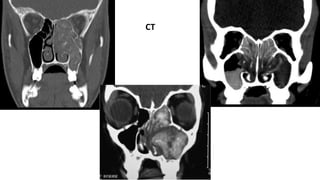

• Radiology: Sinus opacification with areas of hyper

attenuation, cheesy or clay like debri within the sinus

• CT

NCCT is the imaging of choice

 Opacification of the nasal cavity and one or more paranasal sinuses

 The sinuses are typically opacified by centrally (often serpiginous ) hyperdense

material with a peripheral rim of hypodense mucosa.

 Erosion of bone (skull base and orbit) is seen in 20 - 60% of cases